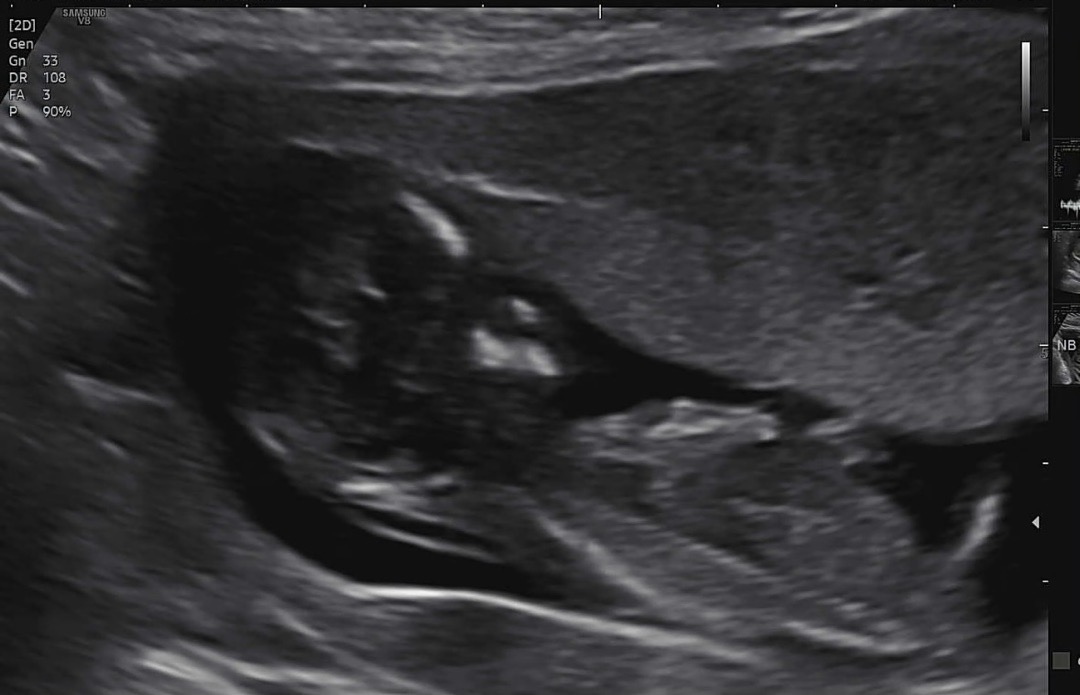

각도법 도사님을 찾습니다! 참견부탁드려용

저도 아들같네요!

오 약간 아들같아용